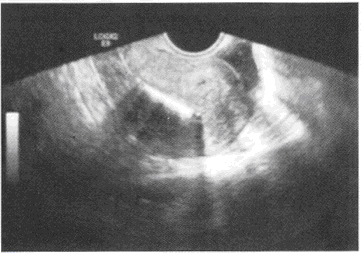

患者,女性,40岁,妇科超声检查:中下腹纵切面如图,强回声所示为

• A.子宫钙化环

• B.宫内节育器

• C.子宫肌瘤

• D.孕囊

• E.子宫肌瘤钙化